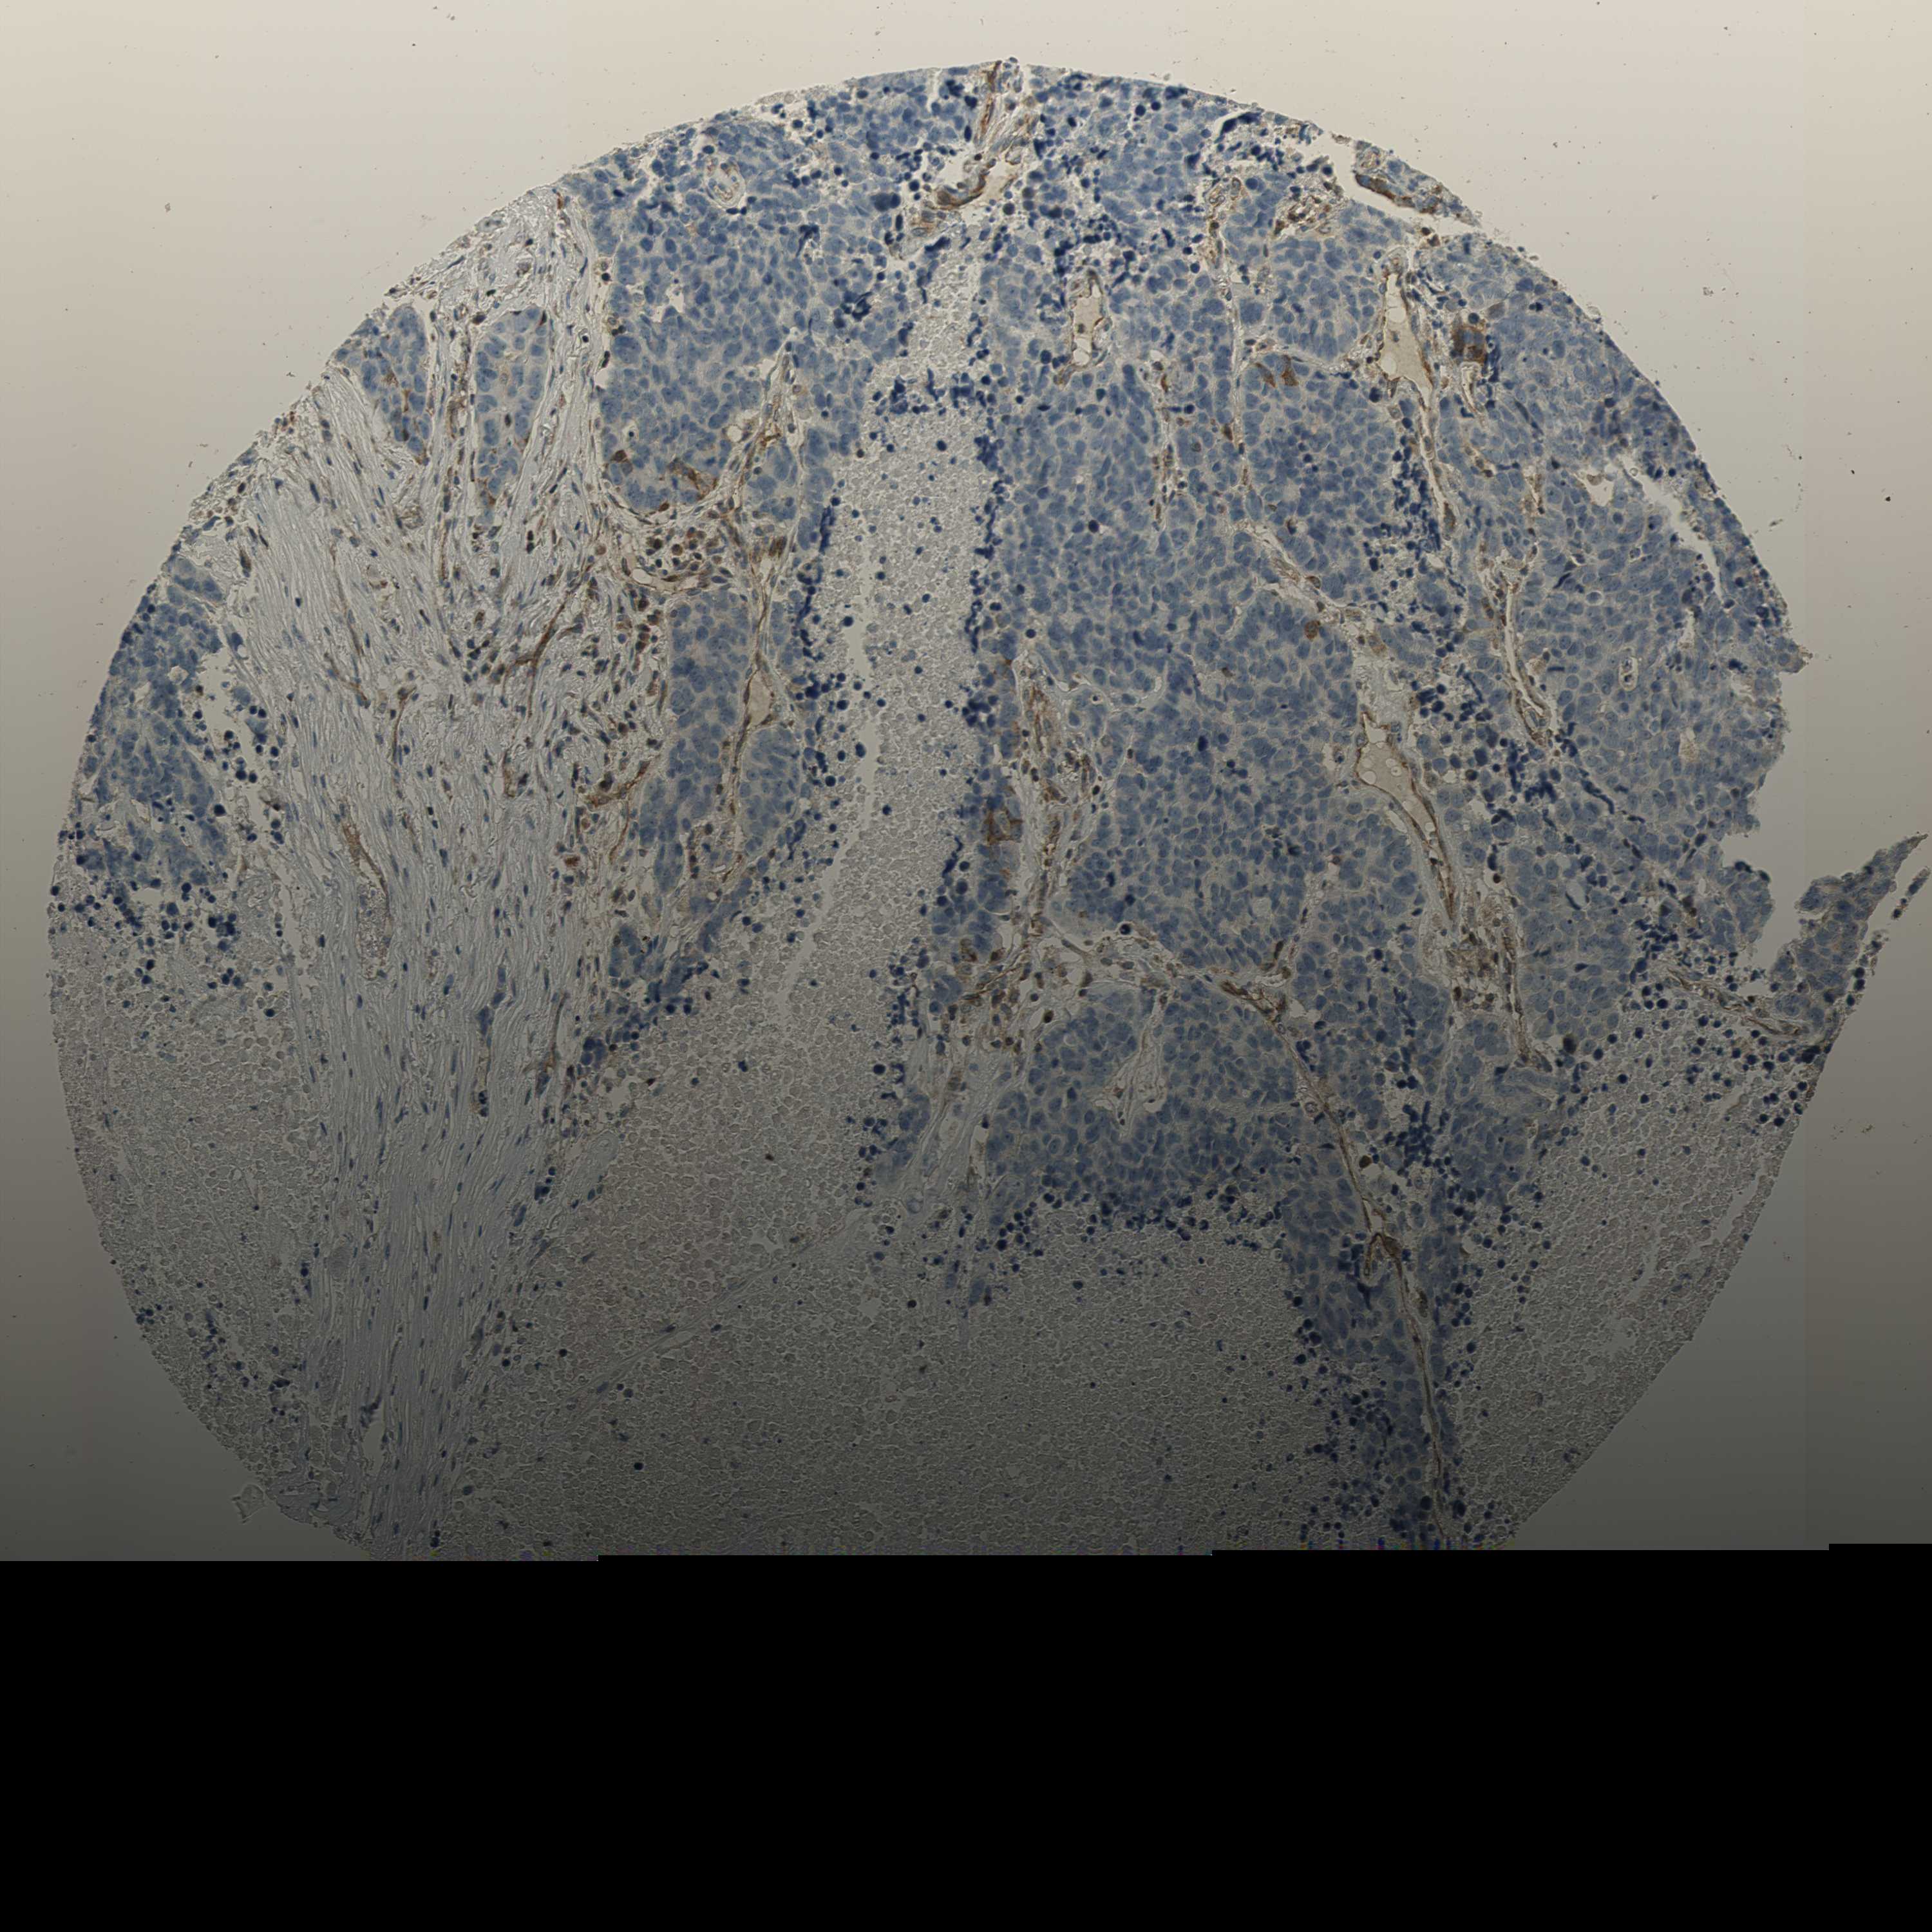

CANCER LUNG CANCER Show tissue menu

LUAD TCGA LUAD VALIDATION LUSC TCGA LUSC VALIDATION PROTEIN LUAD CPTAC PROTEIN LUSC CPTAC PROTEIN EXPRESSION

ANTIBODIES

AND

VALIDATION